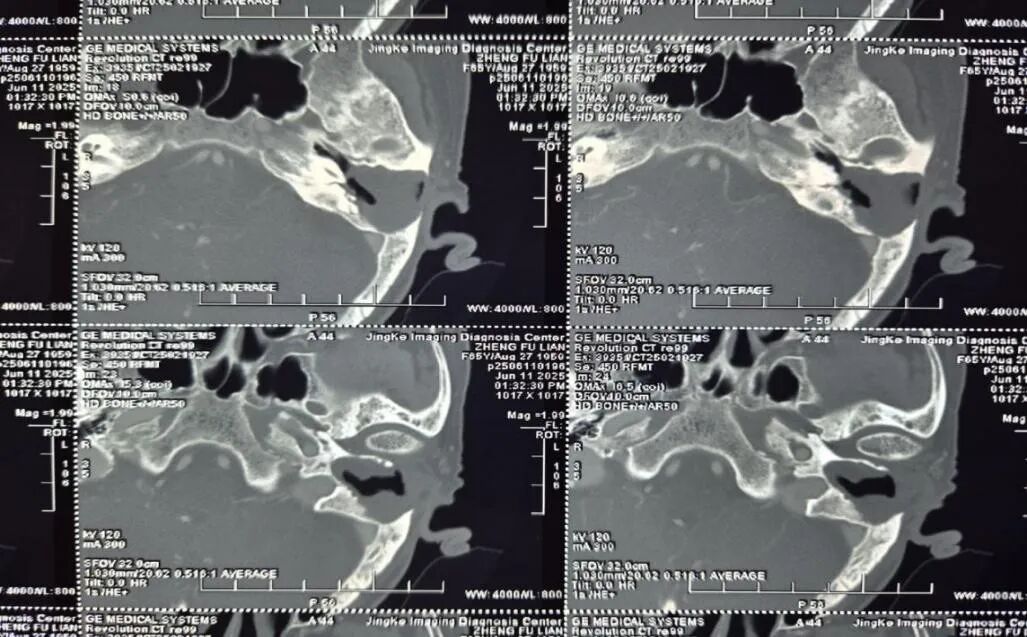

患者因长期耳痛、听力下降且症状反复加重来院就诊,经详细检查确诊为“巨大中耳胆脂瘤”。中耳胆脂瘤虽非真性肿瘤,但具有侵蚀性,可破坏中耳及周围重要结构,若不及时处理,可能引发颅内感染等严重并发症。由于该患者病变范围广泛,已累及颞骨多个关键区域,手术难度大、风险高,对手术团队的技术水平提出了极高要求。

术前,耳鼻喉科团队组织了多次病例讨论,结合影像学检查结果,为患者制定了周密的手术方案,并对可能出现的风险做了充分评估和预案准备。术中,团队在高清显微镜下精细操作,精准分离病变组织与正常结构,成功完成颞骨次全切除,在彻底清除病灶的同时,有效保护了患者的听力相关结构。术后,经过医护人员的精心护理,患者未出现任何并发症,听力功能逐步恢复。